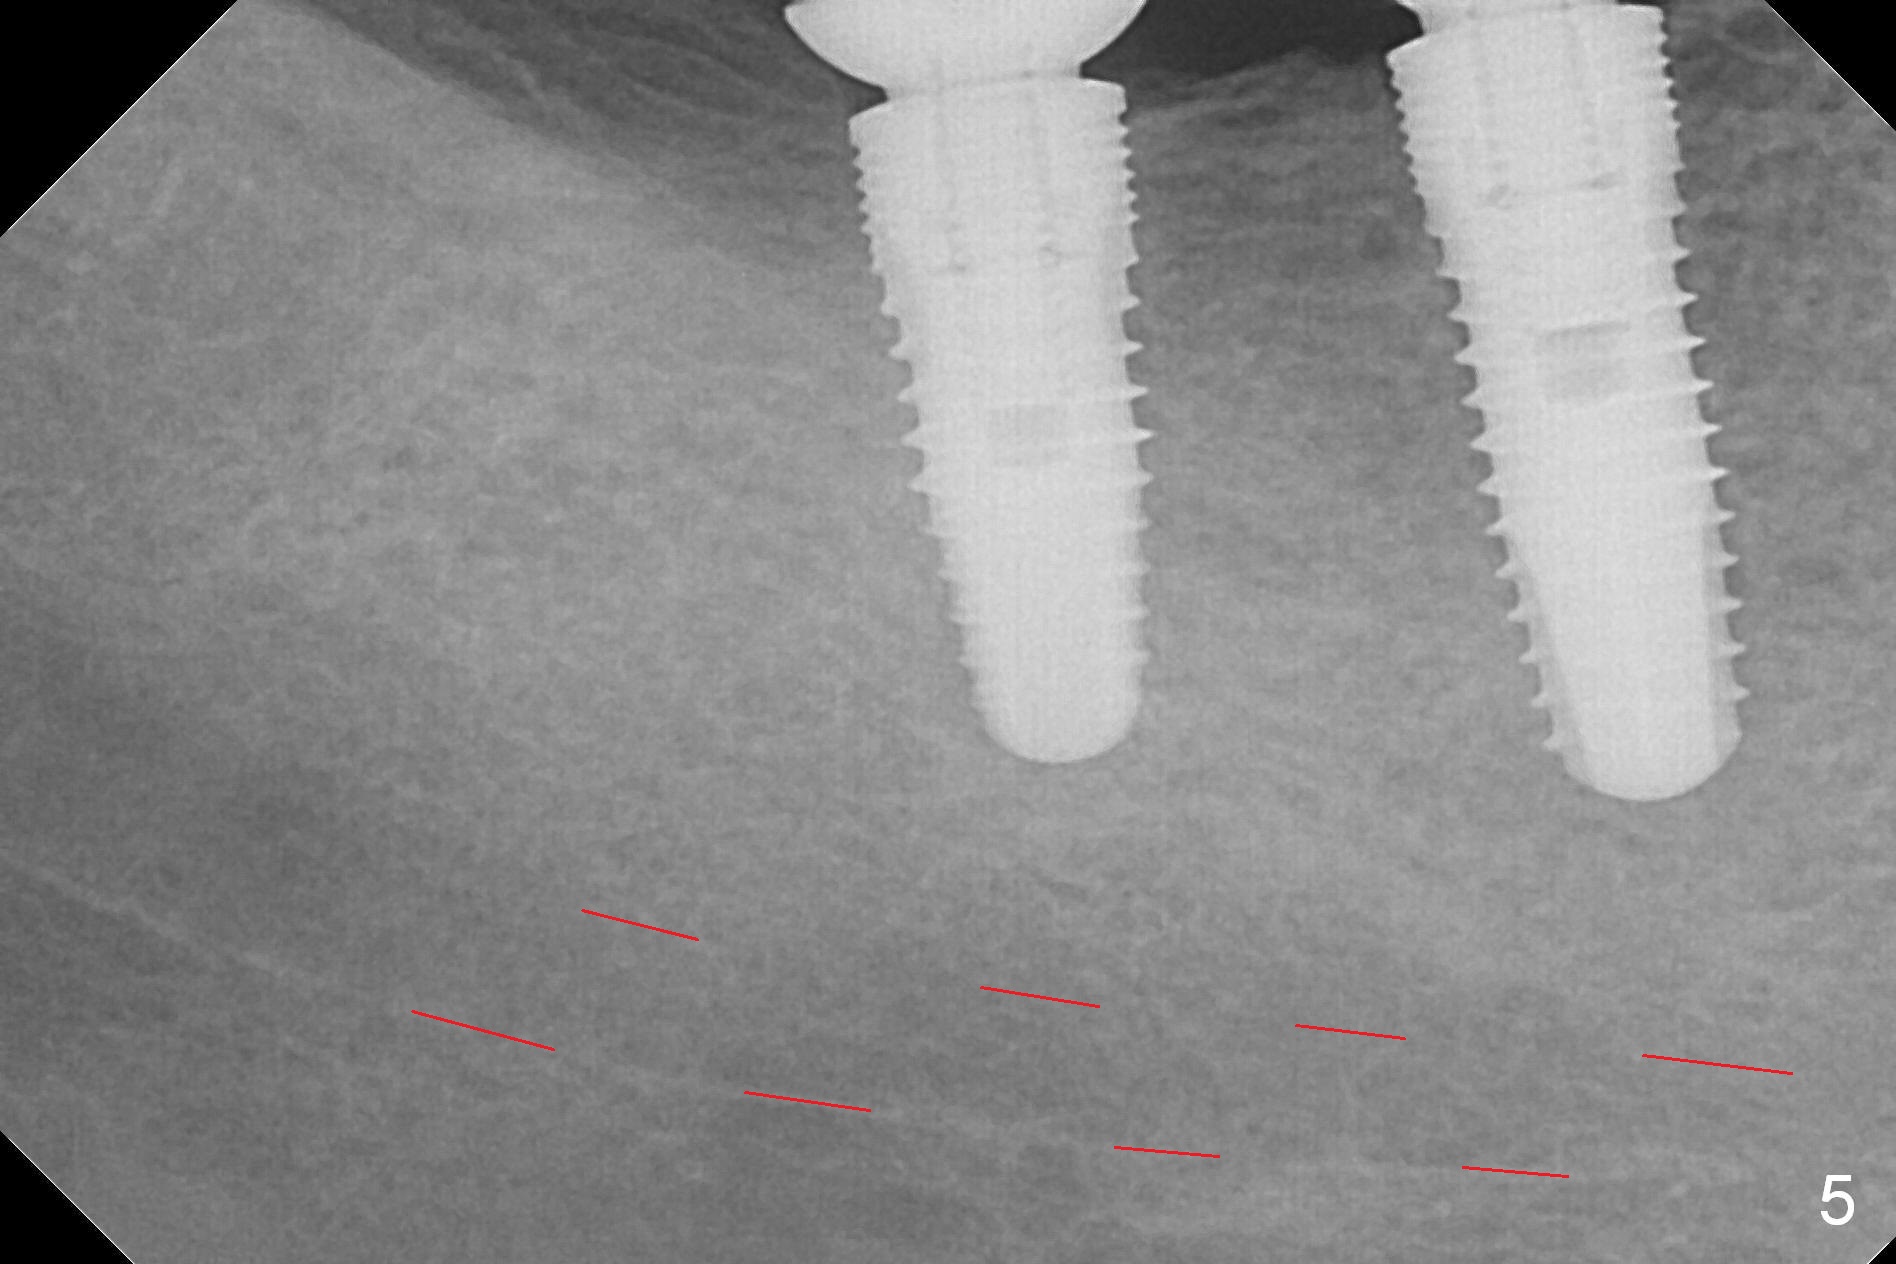

The supraerupted tooth #2 is adjusted using the lower right surgical stent. Osteotomies are initiated by using starter drill through surgical stent over the ridge (Fig.1) prior to incision. The initial depths are 10 and 12 mm at the sites of #31 and 30, respectively (Fig.2). The new sensor with the existing sensor holder cannot reach the deep portion of the lingual vestibule (Fig.2,3). Without the sensor holder, the #2 sensor with rounded corners has no problem showing the Inferior Alveolar Canal (Fig.4 red dashed line). The two implants (5x12 and 5x14 mm, Fig.5) are placed with >50 Ncm. Cemented abutments are immediately placed (6.8x4(2) and 6.8x4(3) mm) to reduce suture tension (after autogenous bone graft and collagen dressing) and hold periodontal dressing in place. The wound does not heal completely 15 days postop (Fig.6). The patient reveals that he smokes 1/2 pack per day. There is crestal bone resorption 4 months postop (Fig.7 *). It appears that for smokers, implants should be smaller, placed deeper and buried. In addition, his oral hygiene is not good.